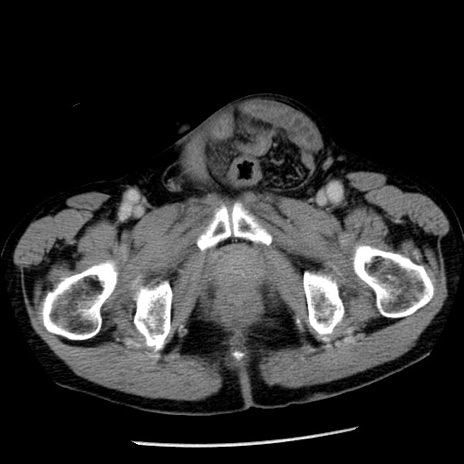

症例26(横断像)

【症例】80歳代男性

【主訴】嘔吐

【現病歴】昨晩2回嘔吐あり、今朝になっても嘔吐あり。来院。

【既往歴】胃潰瘍

【身体所見】意識清明、BT 37.6℃、BP 166/95mmHg、HR 100bpm、SpO2 97%、腹部:平坦・軟、腸蠕動音聴取良好、圧痛なし。

【データ】WBC 21900、CRP 1.46